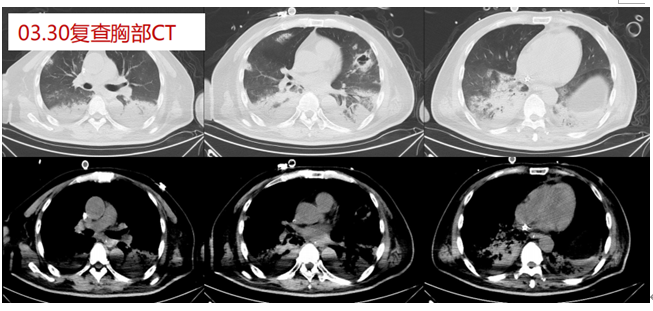

患者,女,52岁,胸闷、气喘2周,加重伴呼吸困难20小时。于2020年3月25日入院,“皮肌炎”病史5个月,规律口服甲泼尼龙、环孢素。胸部CT可见弥漫磨玻璃改变,白肺。第一时间送BALF mNGS,结果回报耶氏肺孢子菌(序列数27115),人类疱疹病毒5型(CMV)(序列数14472),曲霉(序列数3),涂片查到耶氏肺孢子菌,病原学最终诊断:PCP+CMV+曲霉混合感染。给予磺胺+卡泊芬净+更昔洛韦联合治疗,并予以VV-ECMO、IPPV+PPV,最终患者痊愈出院。

图片

治疗前胸部CT

治疗后胸部CT